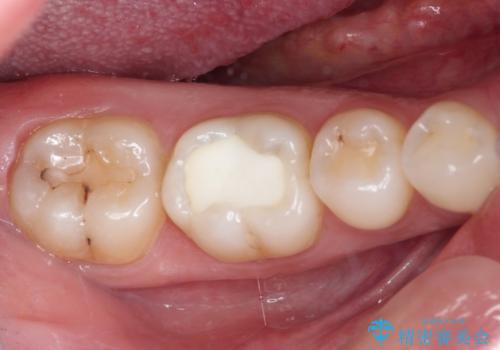

- 他院にてむし歯の治療をし、当院にてセラミックを入れたいとのことで来院された患者様です。

むし歯がないか確認し、セラミックインレーにて修復することとしました。

セラミックインレー装着時には、唾液の侵入を防ぐために、ラバーダム防湿を行いました。